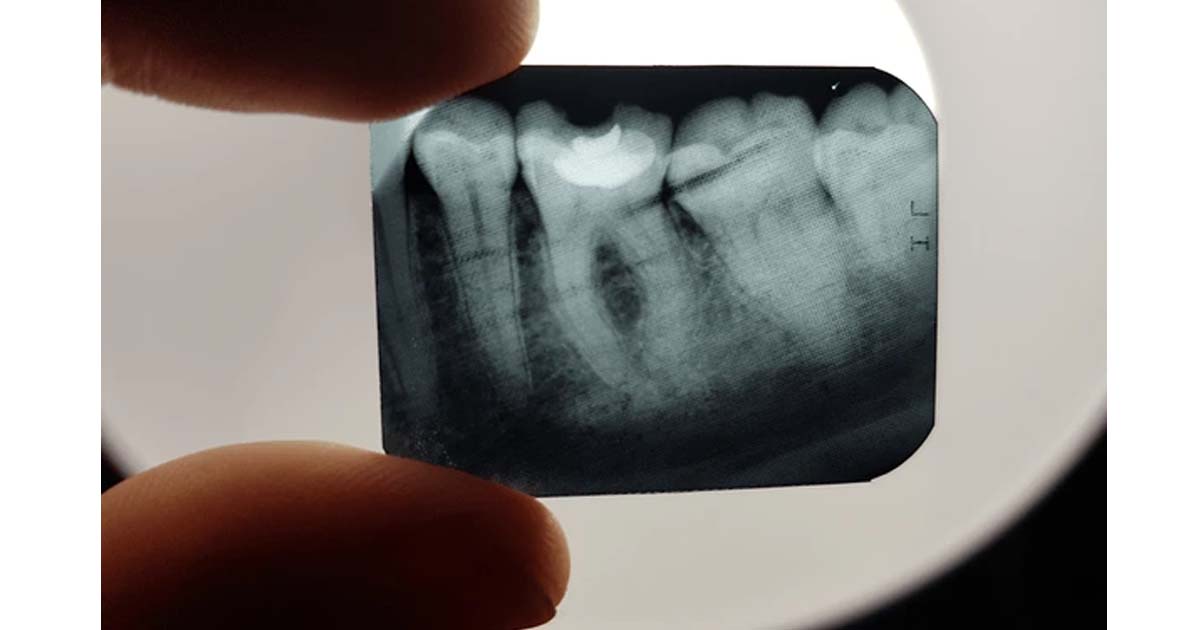

Traditional X-rays:

Traditional X-rays taught in colleges are of no use with the growing demands of digital dentistry in today's world. Students are taught how to develop a dental film in separate developer and fixer solutions in dingy dark rooms. This not only increases the time of diagnosis but also wastes the precious time of students that could be utilized in learning other relevant clinical procedures. X-ray films also have a handling issue as they have to be kept safe until all of the patient’s sittings are completed. Other than that, there is a chance of confusion with different dental films for different patients.

Digital Radiography:

It is a superior imaging technique used in dentistry, wherein electronic sensors generate images of the oral cavity. Students should be taught to handle this equipment regularly rather than relying on traditional films. The reduced processing time, superior image quality, and easy handling make it convenient for dental students and dentists to stay updated with newer technology. This ultimately helps in better diagnosis of dental diseases, leading to improved oral care.